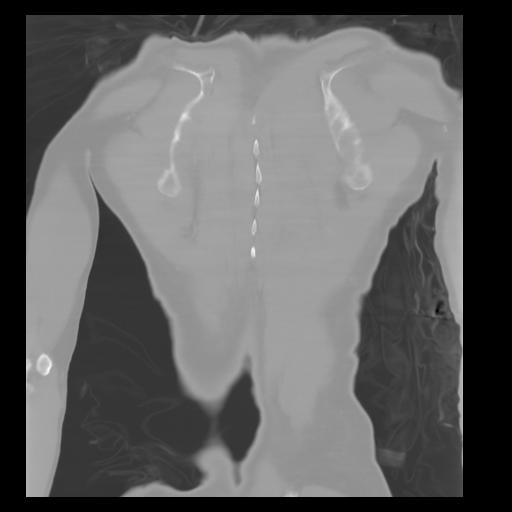

29 CUERPO,CE,Coronal,3.000,CUERPO,Coronal,